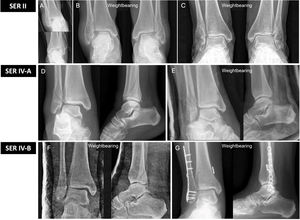

Example of SER 2 fracture. (A) Non-weightbearing X-ray showing bilateral trans-syndesmotic fibular fracture. (B) Weightbearing X-ray MCS maintained (<4mm). It was treated by immediate weightbearing without immobilisation. (C) Weightbearing X-ray at 6 months showing correct fracture healing. Example of a SER 4a fracture. (D) Non-weightbearing X-ray with increased MCS (>4mm). (E) Weightbearing X-ray showing reduction of the medial clear space with loading at 90°. The fracture was managed conservatively with a weightbearing cast. Example of SER 4b ankle fracture. (F) Weightbearing X-ray showing opening of the MCS and asymmetry of the mortise (unstable lesion). (G) Surgery is indicated with open reduction and internal fixation with plate and screws in the fibula and fixation of the syndesmosis by means of a dynamic system.